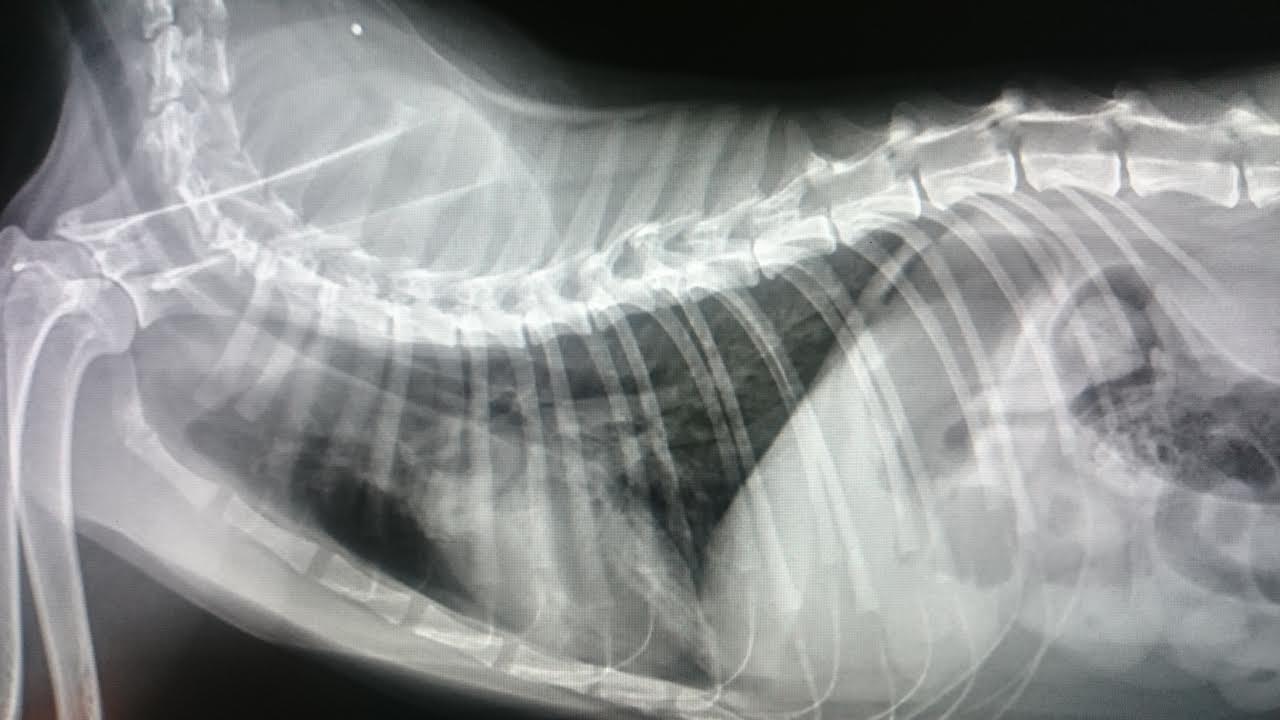

原先因喘息問題住院治療

x光顯示肺部及支氣管有浸潤(發炎)狀況

三日後(3/16)x 光也有逐漸好轉的成像

4/3當日採樣時 小斑又有些許氣喘症狀,x 光顯示肺部跟支氣管有明顯好轉

但是有氣管塌陷的狀況,可能與氣喘有關

住院期間除了做血液檢查及X光外